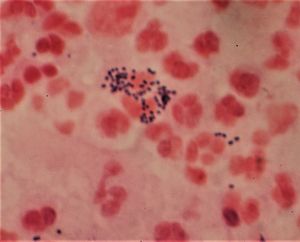

그람 염색은 세균을 그람 양성 세균과 그람 음성 세균으로 분류하는 데 사용되는 염색 기법이다. 1884년 한스 크리스티안 그람이 개발했으며, 세균 감염 진단에 활용된다. 그람 염색은 크리스탈 바이올렛, 아이오딘, 에탄올 또는 아세톤, 사프라닌 또는 카르볼 푸크신을 사용하여 세균의 세포벽 구조 차이에 따라 보라색 또는 분홍색으로 염색한다. 그람 양성 세균은 두꺼운 펩티도글리칸 층 때문에 보라색으로, 그람 음성 세균은 얇은 층과 외막 때문에 분홍색으로 염색된다.

그람 양성 세균은 펩티도글리칸(세포 외막의 50~90%)으로 이루어진 두꺼운 망상 세포벽을 가지고 있어 크리스탈 바이올렛으로 보라색으로 염색되는 반면, 그람 음성 세균은 얇은 층(세포 외막의 10%)을 가지고 있어 보라색 염색을 유지하지 못하고 사프라닌으로 붉은색으로 대비염색된다.

탈색 후 그람 양성 세포는 보라색을 유지하고 그람 음성 세포는 보라색을 잃는다.[17] 대비염색제는 일반적으로 양전하를 띠는 사프라닌 또는 기본 푸크신이며, 탈색된 그람 음성 세균에 분홍색 또는 빨간색을 부여하기 위해 마지막으로 적용된다.[18][19] 그람 양성 세균과 그람 음성 세균 모두 대비염색제를 흡수한다. 그러나 대비염색제는 더 어두운 크리스탈 바이올렛 염색으로 인해 그람 양성 세균에서는 보이지 않는다.

탈색 후 그람양성세균은 보라색을 유지하며 그람음성세균은 보라색을 잃게 된다.[59] 일반적으로 양전하를 띤 사프라닌 또는 염기성 푸크신으로 대비염색을 마지막에 수행하여 탈색된 그람음성세균을 분홍색 또는 빨간색으로 만든다.[60][61] 그람양성세균과 그람음성세균 모두에 대비염색을 한다. 그러나 대비염색을 해도 크리스탈 바이올렛 염색이 더 진하기 때문에 그람양성세균은 여전히 보라색을 띠게 된다.